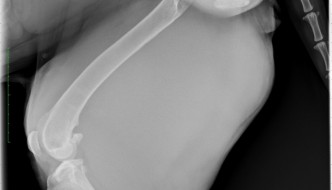

Today's case is a 4-year-old female neutered Mastiff with a 3-week history of a growing mass and lameness. Take a look at the case, and post your comments below. … [Read more...]